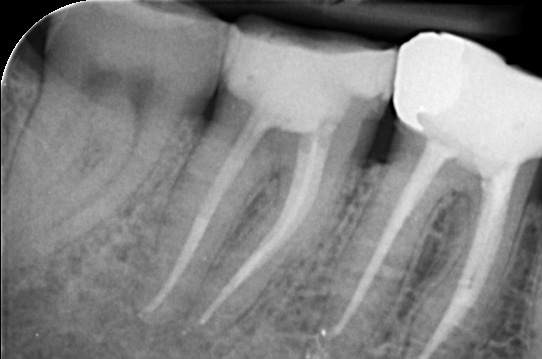

Gallery - Root Canal Treatment

Case 6

Before After